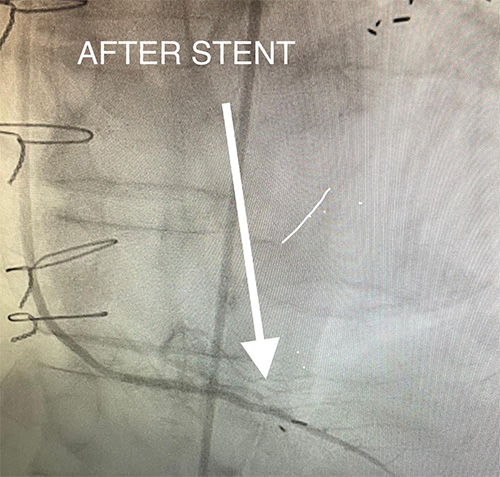

82 y/o man presents with new, worsening chest pain. He’s had a history of bypass surgery and multiple stents placed in the past. He was referred for coronary angiogram. Findings are seen in the “ Before” picture, followed by the therapeutic stent placed.